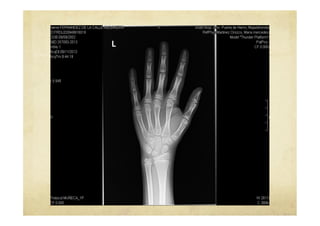

Imagen radiológica del déficit del

gen Shox

Talla baja: GenShox, Fenotipo !   Talla baja y fenotipo variable poco específico en niños preescolares !   Deformidad de Madelung (acortamiento e incurvación del radio con subluxación distal del cúbito) !   Acortamiento mesomélico, acortamiento de los huesos de carpo y el tarso !   Paladar ojival, escoliosis, micrognatia, hipertrofia muscular !   La ausencia de estos signos no descarta el déficit del gen Shox

Imagen radiológica deldéficit del gen Shox